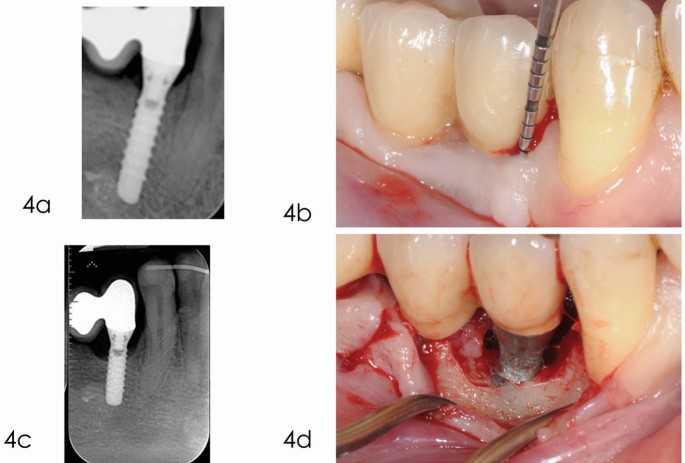

Peri-implantitis는

● 임플란트 주변 연조직의 염증 증가,

● 방사선 사진에서 확인되는 임플란트 주위 골소실(bone loss)

이 동시에 나타나는 상태다.

③ 재생치료 (Regenerative therapy)

● 골재생재료(Bone graft)

● 차폐막(GBR)

● EMD(에나멜기질단백)

● 콜라겐 기반 바이오재료

재생 여부는 골벽 수에 따라 결정된다.

3~4벽 골 결손 → 재생 가능

1벽 결손 → 재생 효과 낮음

5-5. 골재생술(Regenerative surgery)

적용 조건

3~4벽 결손에서 예후 가장 좋음.

사용하는 재료

- 이종골(xenograft)

- β-TCP

- 콜라겐 멤브레인

- Emdogain(EMD)

2023년 JOMI:

재생술 시행 시 5년 생존율이 77% → 93%로 증가.